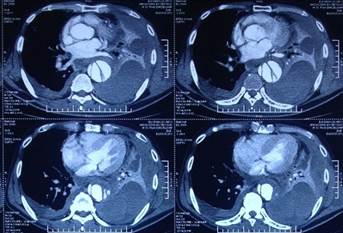

Ảnh: Hybrid trên quai ĐMC và tổn thương nhiều tầng của mạch máu:

Lóc tách type B vỡ vào khoang màng phổi T